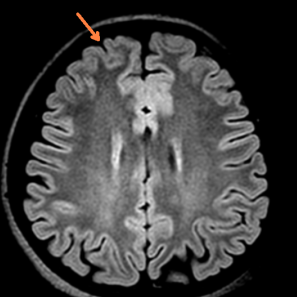

术前影像学评估(头颅MRI提示:考虑左侧额叶白质区点状缺血灶,但细看右额极似有脑发育不良,PET-CT提示右侧额极、扣带回低代谢